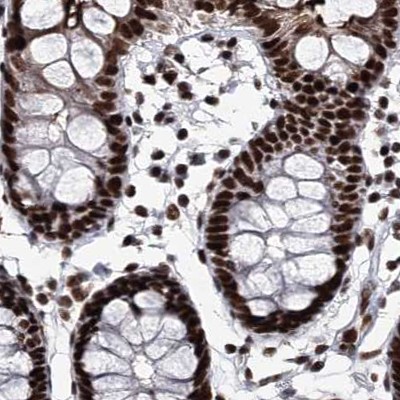

Immunohistochemical staining of human cerebral cortex, colon, kidney and testis using Anti-SCAF8 antibody HPA035602 (A) shows similar protein distribution across tissues to independent antibody HPA035601 (B).